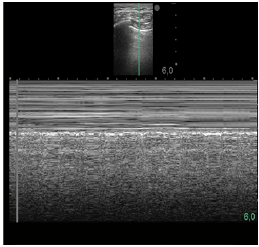

Um paciente de 50 anos de idade encontra-se, internado na UTI por conta de choque séptico de foco pulmonar, em ventilação mecânica na modalidade pressão e no modo assisto-controlado. Pela manhã foi submetido a acesso venoso central em veia axilar guiado por ultrassonografia. Ao exame físico, notou-se que o paciente está com hipotensão e taquicardia. A primeira hipótese diagnóstica é pneumotórax e é realizada radiografia com imagem apresentada.

Qual imagem abaixo corresponde ao achado ultrassonográfico para o paciente em questão?